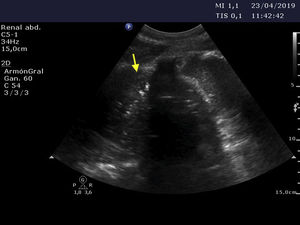

An 85-year-old woman was seen in the emergency room with dizziness following a traffic accident. After a few hours she developed breathing difficulties, desaturation and the absence of vesicular murmur upon auscultation. Pulmonary ultrasound evidenced a “C pattern” in the left hemithorax, with peristaltic motion (Fig. 1), and the chest radiographs (Fig. 2) and thoracoabdominal computed tomography scan (Fig. 3) confirmed the diagnosis of diaphragmatic rupture with bowel loop herniation towards the left thoracic space. Emergency surgical repair was carried out and the patient was discharged from intensive care after 5 days. Diaphragmatic rupture often proves fatal – hence the importance of tools allowing early diagnosis and treatment, since they condition the prognosis in such cases.